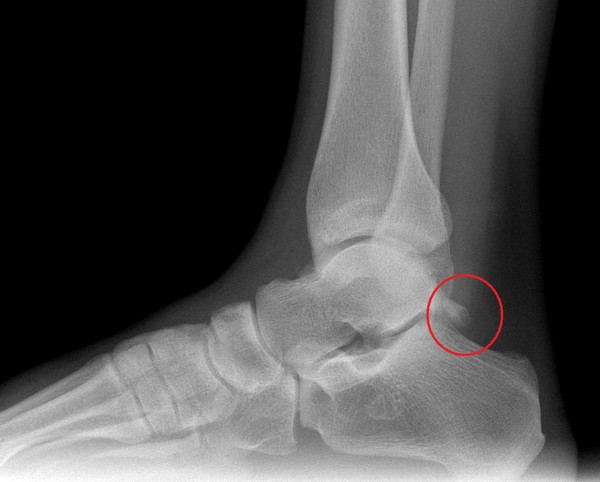

| Hình ảnh chiếc xương thừa của Ronaldo. |